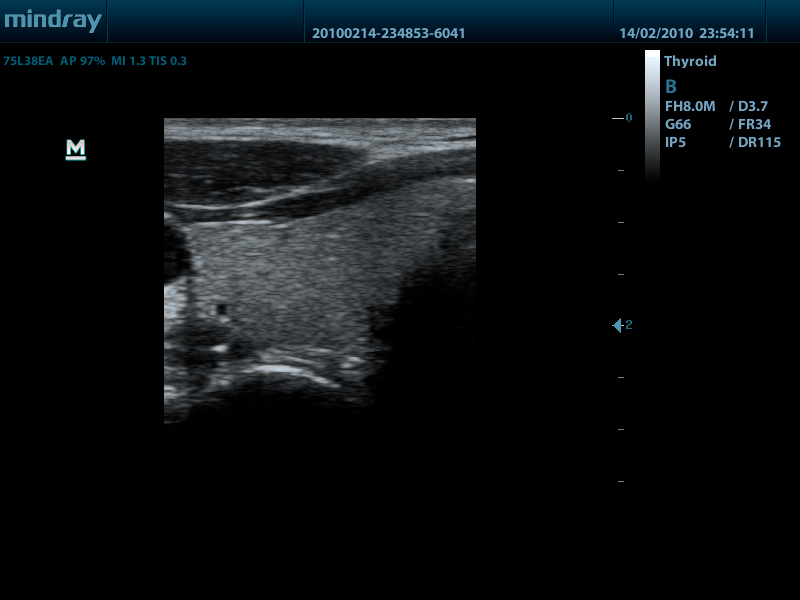

Линейный датчик 75L38EA (5.0/7.5/8.5/10.0/Н8.0/Н10.0 МГц, 38 мм)

Mindray DP-50 – портативная цифровая ультразвуковая система с ЖК монитором 15 дюймов (1024Х768)

- диапазон сканируемых частот от 2,0 до 14,0 МГц

Качество изображения:

- iBeam: функция улучшения разрешающей способности изображения

- iClear: функция подавления шумов на изображении для улучшения детализации и контрастности изображения